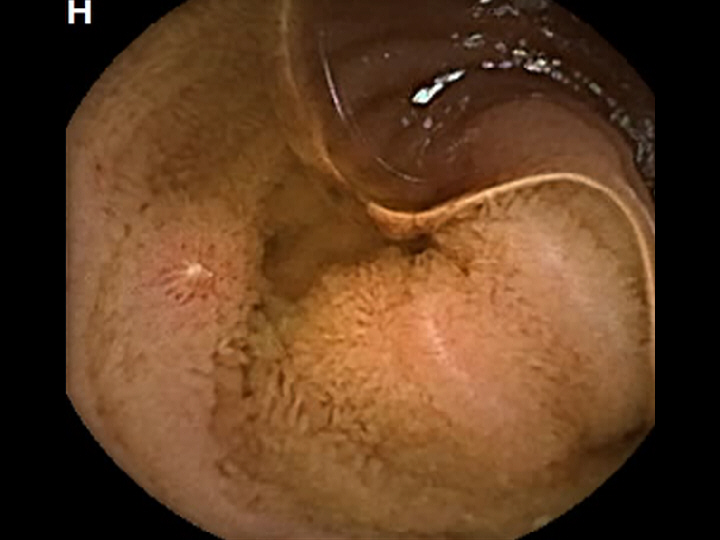

CAPSULE ENDOSCOPY: Crohns Disease: Aphthous Ulcerations in the Small Bowel

Crohns Disease: Aphthous Ulcerations in the Small Bowel. Just click on a picture!

Crohns Disease: Aphthous Ulcerations in the Small Bowel